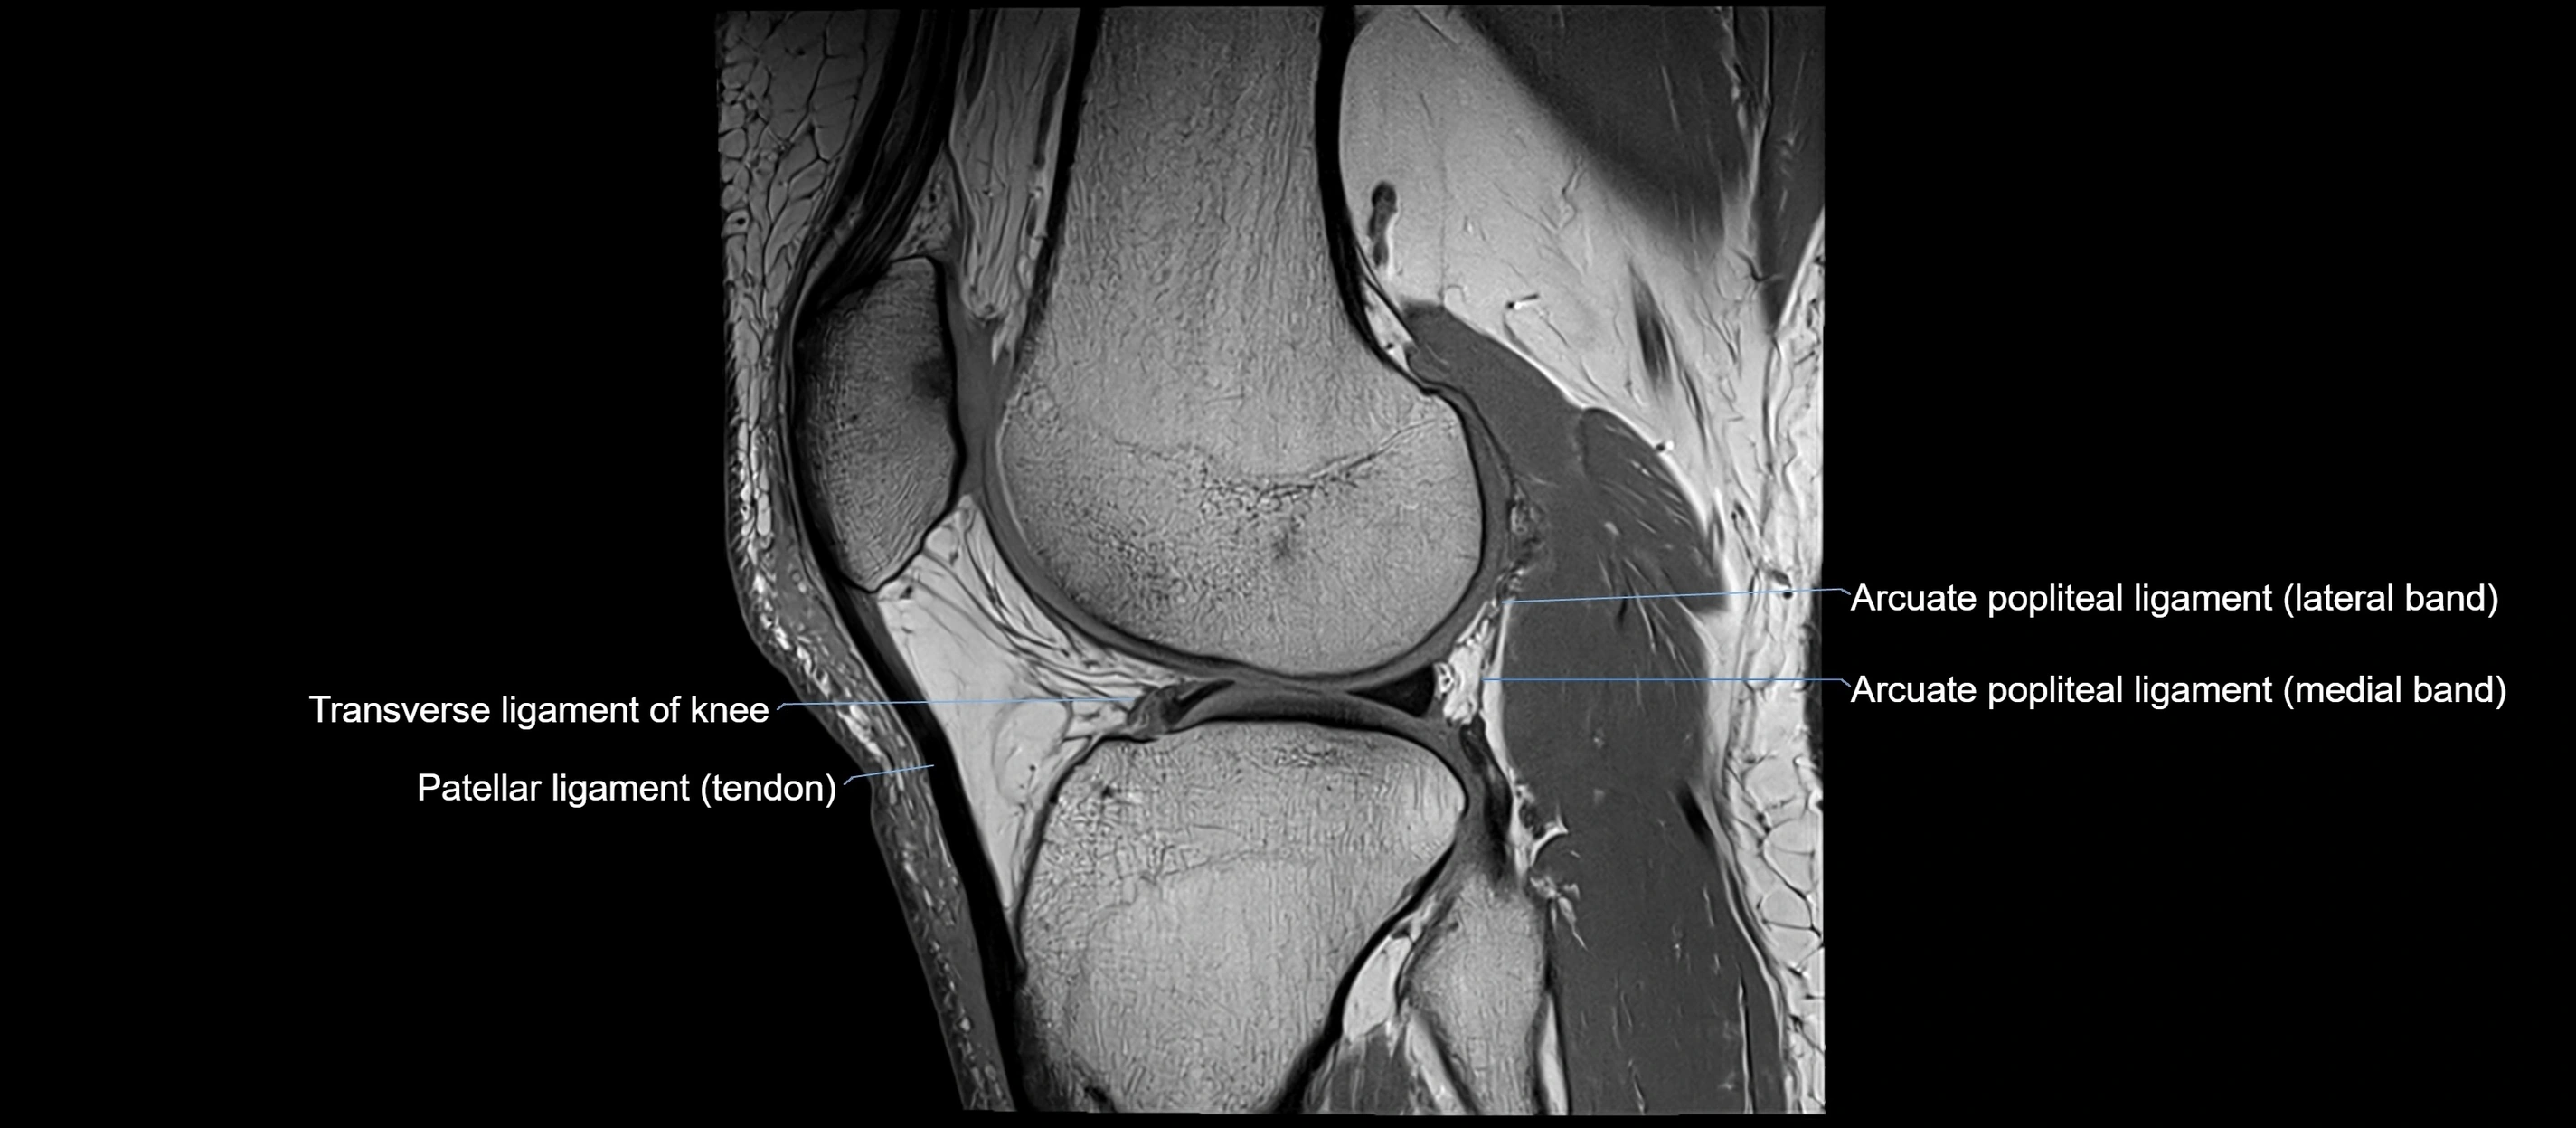

MRI images

image

MRI Appearance

T2-weighted images:

• Normal ACL remains low signal

• Partial or complete tears appear as discontinuity, increased signal, or fiber laxity

STIR (Short Tau Inversion Recovery):

• Normal ACL shows dark low signal

• Acute injury shows bright hyperintensity due to edema and hemorrhage